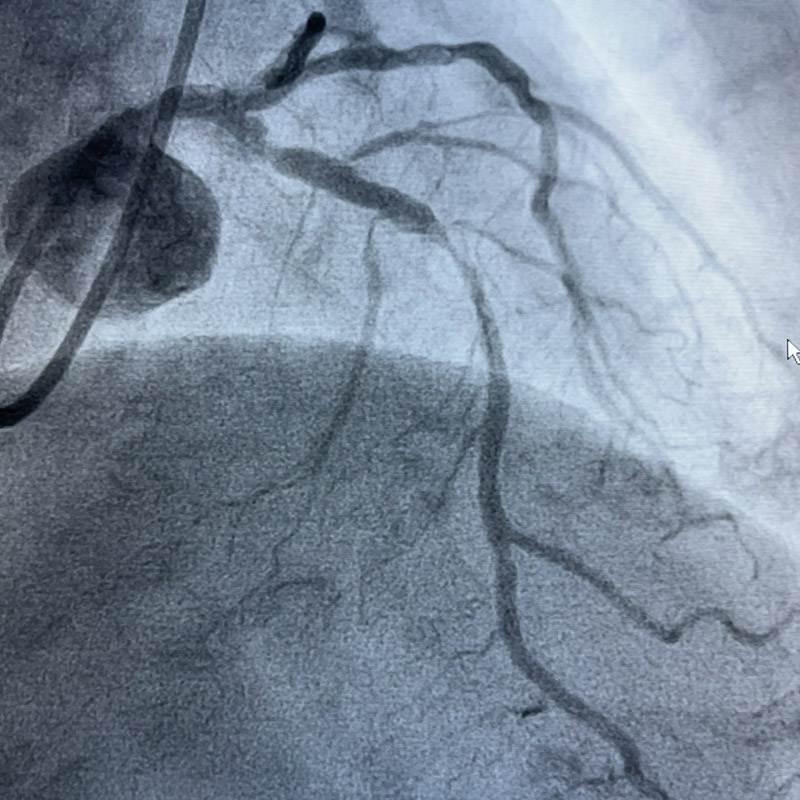

75歲的高齡患者莫阿姨今年九月初曾因突發(fā)胸痛在外院做了支架置入術(shù),11月28日,又出現(xiàn)了胸痛癥狀,遂來到了柳州市人民醫(yī)院。經(jīng)復(fù)查患者冠脈造影提示前降支嚴(yán)重鈣化、迂曲,前降支近段原支架嚴(yán)重膨脹不全,殘余狹窄明顯,如果不及時處理,會出現(xiàn)支架內(nèi)血栓、支架內(nèi)再狹窄等潛在風(fēng)險,嚴(yán)重威脅患者生命!

術(shù)中,心血管內(nèi)科介入團(tuán)隊將Shockwave C2 IVL 3.0*12mm 震波球囊置入前降支病變處,以4-6atm進(jìn)行擴(kuò)張后觸發(fā)8次10秒沖擊波,實施鈣化斑塊碎裂術(shù),術(shù)后支架膨脹不全處明顯擴(kuò)張,并順利于前降支近中段植入1枚支架。復(fù)查IVUS可見鈣化斑塊碎裂,支架貼壁和膨脹良好,血管擴(kuò)張成形滿意,術(shù)后患者胸痛癥狀明顯好轉(zhuǎn)。

▲ 震波前、后造影對比圖